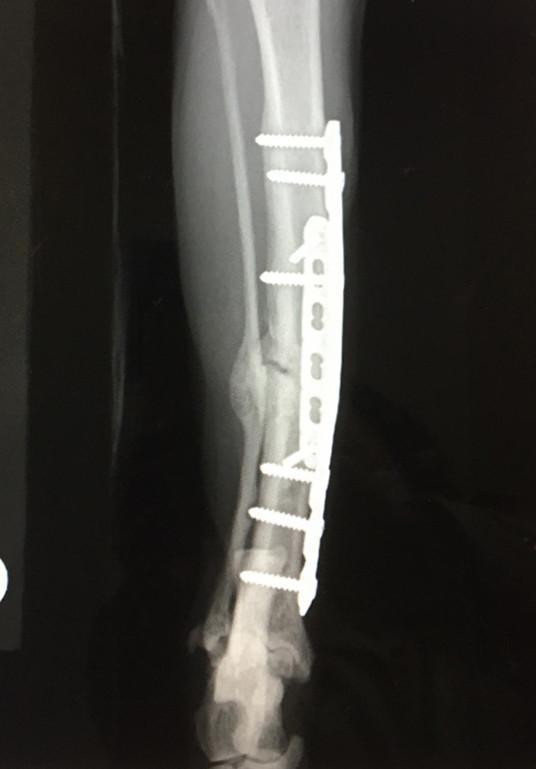

3月10日 手術から8ヶ月後

プレート抜去手術(1回目)

補助プレート(ボルト2本)と内側のボルト2本抜去。

骨形成が進んでいて、取るのが結構大変だった。

隔離部屋再開、1週間エリザベス&ケージレスト&隔離部屋のみ生活。

3月17日 手術から8ヶ月 後

地元病院で抜糸 4針

翌日ケージレスト終了